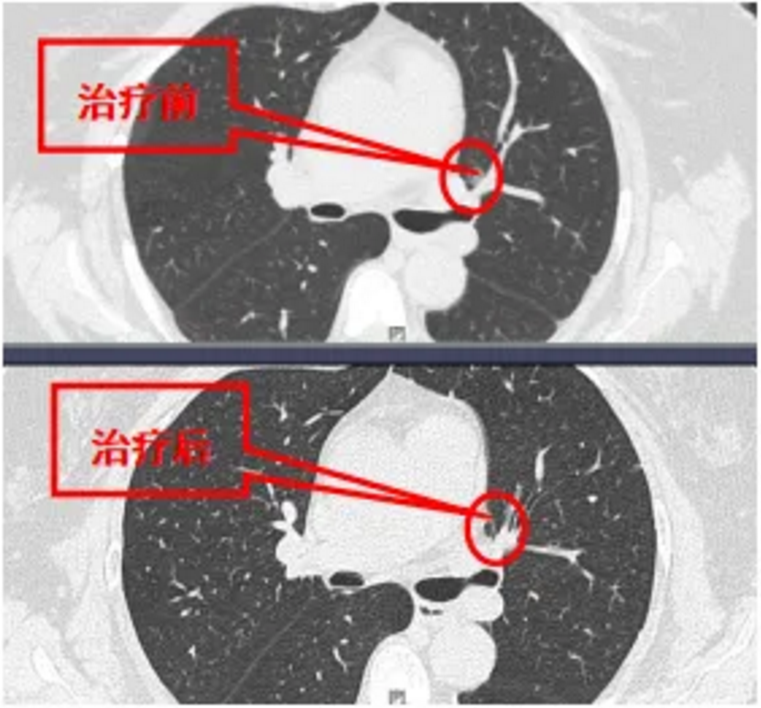

67岁男性患者,经评估行化疗+免疫治疗转化后最终成功手术切除。

左肺门磨玻璃结节,消融治疗后1年随访,结节消失,瘢痕吸收。